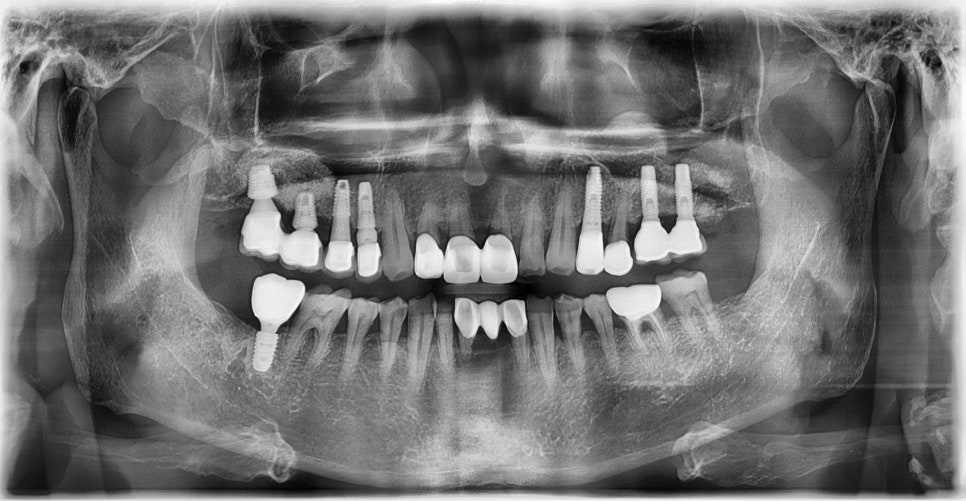

본 환자는 81세 남환으로 오른쪽 아래 어금니가 씹을 때 아프고 찬물에도 시리다며 내원하셨습니다. 고혈압 병력이 있으셨으며 혈압조절 목적으로 매일 혈압약 복용중이라고 하셨습니다.

초진 X-ray (2024-8-16)

치아 발치시 지혈에 큰 문제가 없어 내과 협진 후 고혈압약은 중단하지 않고 임플란트 수술 진행하기로 하였습니다. 수술 후 통증도 없고 지혈도 잘 되어 환자분께서 너무 만족하셨습니다. 감염 예방 목적으로 처방해드린 약은 모두 복용하시도록 안내드렸습니다. 임플란트 수술 약 3달 후 보철물을 장착하였습니다.

임플란트 픽스쳐 식립 (2024-8-27)

보철물 장착 (2024-11-5)